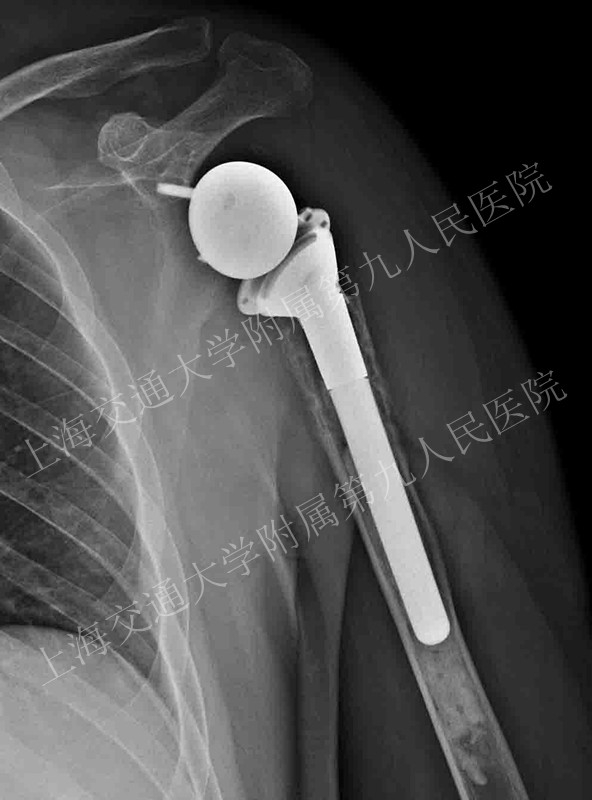

近期在戴尅戎院士领衔下,上海交通大学附属第九人民医院尝试将数字导板反式肩关节置换技术引入肩关节外科领域,该技术的应用对于在复杂的反式肩关节置换术中选择合适的假体以及调整假体后倾角和进行关节盂锉骨准备等操作中发挥很好的辅助作用。

术后效果